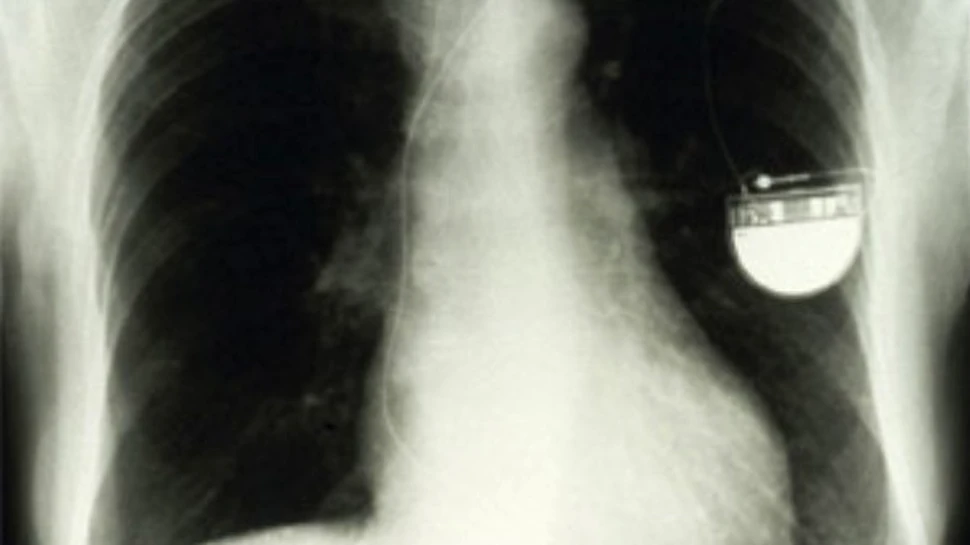

O pacienta de la spitalul St.Francis din New York este in prezent monitorizata de la distanta prin intermediul unui nou pacemaker Wi-Fi. Acesta transmite medicului si seviciul de urgenta informatii cu privire la starea pacientei.

Carol Kasyjanski, 61 de ani, din New York nu se numara printre persoanele care protesteaza din cauza poluarii electromagnetice generate de tehnologia  WiFi. De cateva saptamani i-a fost implantat un nou tip de pacemaker, care comunica wireless cu spitalul, monitorizandu-i activitatea cardiaca. Dupa 20 de ani in care a trait gratie unui pacemaker traditional, Carol se simte de-acum mult mai linistita, intrucat in eventualitatea unei probleme cardiace, noul pacemaker-ul pe care-l are implantat va contacta imediat medicul si serviciul de ambulanta. Tehnologia in sine nu reprezinta nimic nou sub soare: un pacemaker caruia i-a fost adaugat un transmitator radio, un panou de control de instalat in casa pacientului si serverele la spitalul unde acesta este arondat (pacemaker-ul comunica informatiile monitorului aflat in casa, care la randul lui le transmite serverului). In plus, frecventele utilizate pentru transmiterea pretioaselor date sunt diferite de cele dedicate WiFi-ului comercial.

Avantajele tehnologiei nu se limiteaza insa la situatiile de urgenta: pacemaker-ul WiFi usureaza monitorizarea si tratamentul cardiopaticilor si de altfel, potrivit profesorului Steven Greenberg, director al Centrului pentru aritmie si  pacemakere de la spitalul St. Francis din New York, actualul pacemaker este doar primul pas in realizarea de noi dispozitive tot mai inteligente, in masura sa monitorizeze si alti parametri vitali. “In scurt timp vom reusi sa monitorizam tensiunea sanguina, sa masuram glicemia si o sumedenie de alti indicatori fiziologici”, a precizat Greenberg.